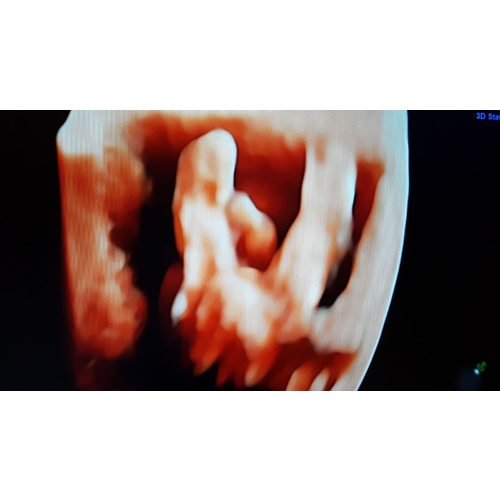

Ik heb nog even contact met haar gehad en ze stuurde me ook de nub nog toe en het beeld in 3d wel mogen we de 12e nog eens terug omdat ze toe gaf zelf ook te hebben getwijfeld en bang is dat onze twijfels daar door komen.. al ben ik aan de hand van de nub en het 3d beeld echt zeker dat het een meisje is toch fijn dat we even extra mogen kijken

Echo met 14 weken, jongetje ( al ben ik zelf nog wat sceptisch omdat het zo vroeg was ) 🙈